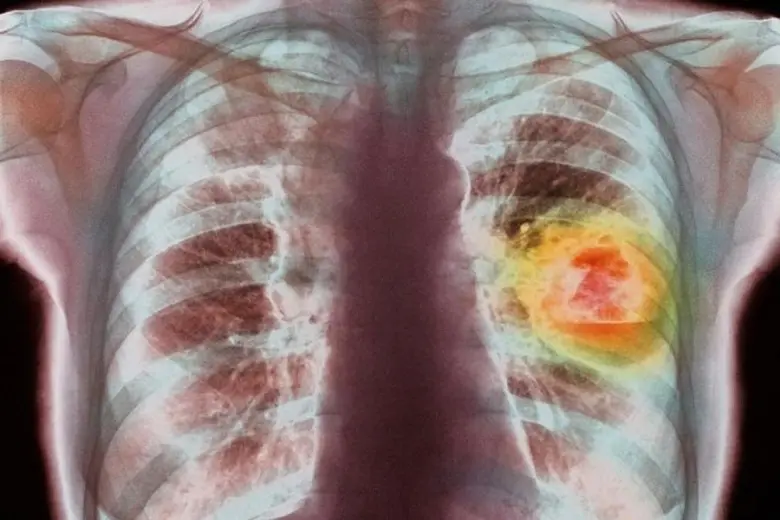

ในปี 2565 มีผู้ป่วยเป็นจำนวนมากที่ตรวจพบว่าเป็นโรคมะเร็งปอดในประเทศไทย ซึ่งยังคงเป็นสาเหตุของการเสียชีวิตเป็นอันดับ 2 ของคนไทย (ในผู้ชายรองจากมะเร็งตับและเป็นอันดับ มะเร็งตับ ในผู้หญิง) ซึ่งการตรวจคัดกรองให้พบโรคมะเร็งปอดในระยะแรกนั้นทำได้ยาก จึงทำให้มีอัตราการตายสูง โดยผู้ป่วยเหล่านี้มากกว่าครึ่งที่ตรวจพบ มักจะเจอในระยะลุกลามเนื่องจากอาการของโรคนี้มักไม่มีอาการส่งผลทำให้ผู้ป่วยได้รับการวินิจฉัยล่าช้า อย่างไรก็ตามก็ยังมีผู้ป่วยจำนวนมากที่สามารถรักษาแต่กลัวการผ่าตัด เนื่องจากในยุคเริ่มต้นของการผ่าตัดปอดนั้น ได้ริเริ่มทำโดยการเปิดช่องอก ซึ่งมีความจำเป็นในการที่ต้องตัดกล้ามเนื้อหลายมัดและถ่างขยายกระดูกซี่โครงในการเข้าไปทำการผ่าตัดจึงทำให้ผู้ป่วยค่อนข้างกังวลและเกิดอาการกลัวในการรักษาโรคมะเร็งปอด

รศ.นพ.ศิระ เลาหทัย แพทย์ผู้เชี่ยวชาญศัลยศาสตร์ทรวงอกเฉพาะทางด้านการผ่าตัดส่องกล้องในช่องทรวงอก โรงพยาบาลวชิรพยาบาลกล่าวว่า ในยุคฝุ่น PM.25 มหันตภัยด้านมลพิษคุกคามคนไปทั่วโลก ส่งผลให้เกิดความเสี่ยงจากโรคมะเร็งปอดมากขึ้น … ผู้ป่วยเข้ามารับการรักษามากขึ้น อีกทั้งยังพบผู้ป่วยโรคมะเร็งปอดที่มีอายุที่น้อยลงมากขึ้นเรื่อย ๆ ปัจจุบันมีคำถามยอดฮิต เช่น ผมเจอมะเร็งปอด แล้วผมอยู่นานรึเปล่า? แล้วจะมีโอกาสรอดหรือมั้ย ? ซึ่งจากสถิติของข้อมูลจากสถาบันมะเร็งนานาชาติ พบว่าหนึ่งในโรคมะเร็งที่พบได้บ่อยที่สุดในโลก